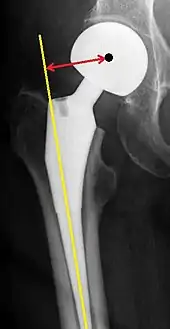

Post-operative projectional radiography is routinely performed to ensure proper configuration of hip prostheses.

The direction of the acetabular cup influences the range of motion of the leg, and also affects the risk of dislocation.[7] For this purpose, the acetabular inclination and the acetabular anteversion are measurements of cup angulation in the coronal plane and the sagittal plane, respectively.

Center of rotation: The horizontal center of rotation is calculated as the distance between the acetabular teardrop and the center of the head (or caput) of the prosthesis and/or the native femoral head on the contralateral side.[78] The vertical center of rotation instead uses the transischial line for reference.[78] The parameter should be equal on both sides.[78]